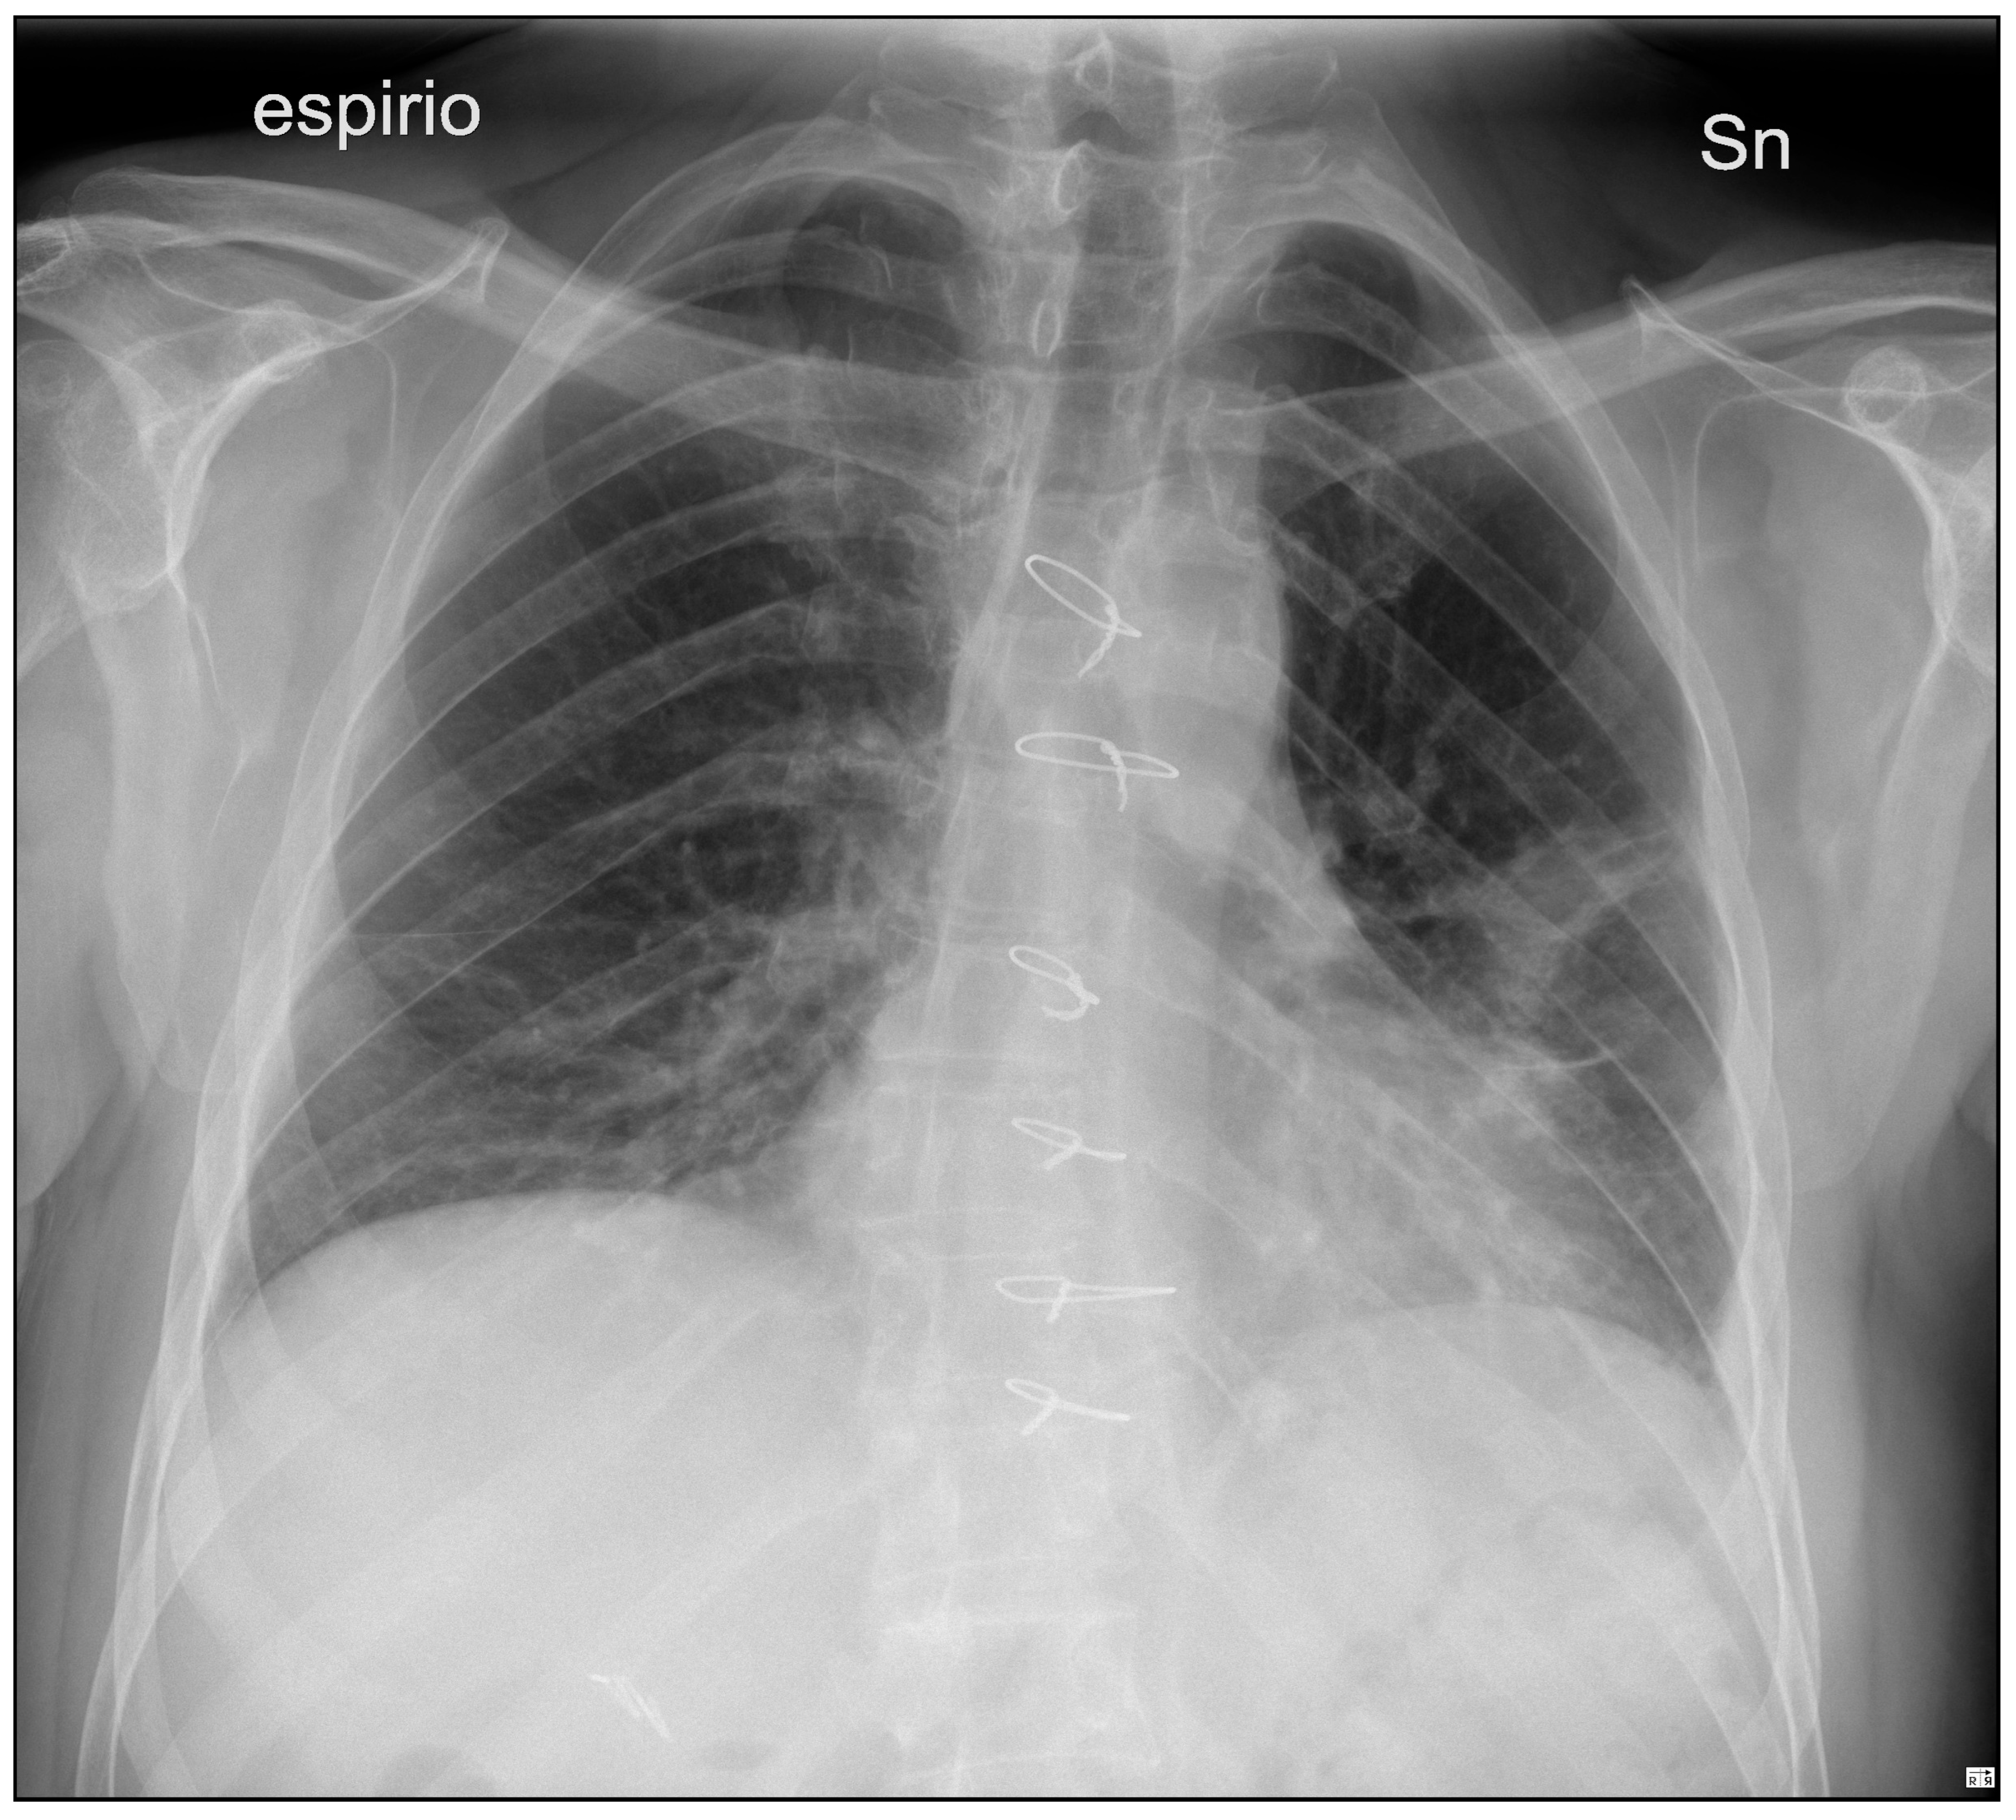

The postoperative course took place in the Intensive Care unit for nine days, during which the patient received blood transfusions (2 units), vasopressor support, antibiotic therapy and steroids. Bronchial toilet was performed twice to free of blood and secretions the tracheobronchial tree. Due to the occurrence of a fever and a rise in the inflammation markers a CT scan was ordered on p.o. day 3, showing an intraparenchymal hematoma (6 cm) in the left upper lobe (LUL), without active bleeding spots (Figure 2A). A conservative approach was chosen and the fever progressively subsided, blood tests gradually normalized and the hematoma progressively shrunk (Figure 2B). The patient returned to the ward on the 9th p.o. day and was discharged from the hospital on p.o. day 20. A chest film obtained a month later revealed almost complete reabsorption of the hematoma, with a very satisfactory lung re-expansion (Figure 3). Data regarding preoperative parameters, intraoperative steps and postoperative events are reported in Table 1.

Figure 2. Postoperative sequential chest CT scans showing parenchymal LUL hematoma (A) and initial shrinking at CT follow-up (B).